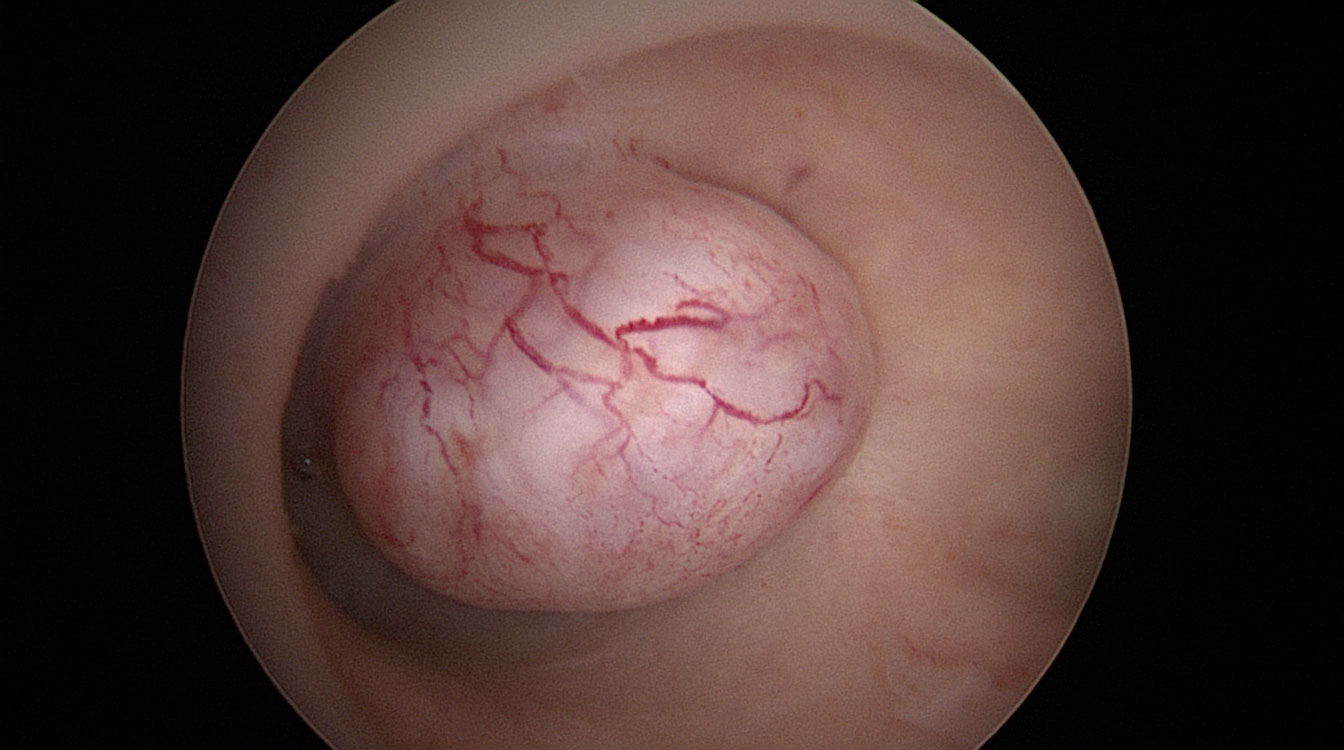

Sindrom Asherman (Sinechia uterină)

Țesutul cicatricial și aderențele din cavitatea uterină (fig. 7, 8) pot apărea după chiuretaje uterine, o intervenție chirurgicală uterină anterioară sau pot fi urmarea unei infecții. Prezența acestor aderențe oferă un mediu intrauterin nefavorabil implantării embrionului. Dacă aderențele sunt extinse la întreaga cavitate uterină pot determina absența menstruației. În timpul histeroscopiei aceste aderențe pot fi secționate cu ajutorul unor foarfeci speciali ce permit astfel refacerea cavității uterine (fig. 14). După operație, un mic balon poate fi introdus temporar în cavitatea uterină pentru a împiedica reapariția aderențelor sau pot fi utilizate geluri (ce conțin acid hialuronic) ce au același rol.